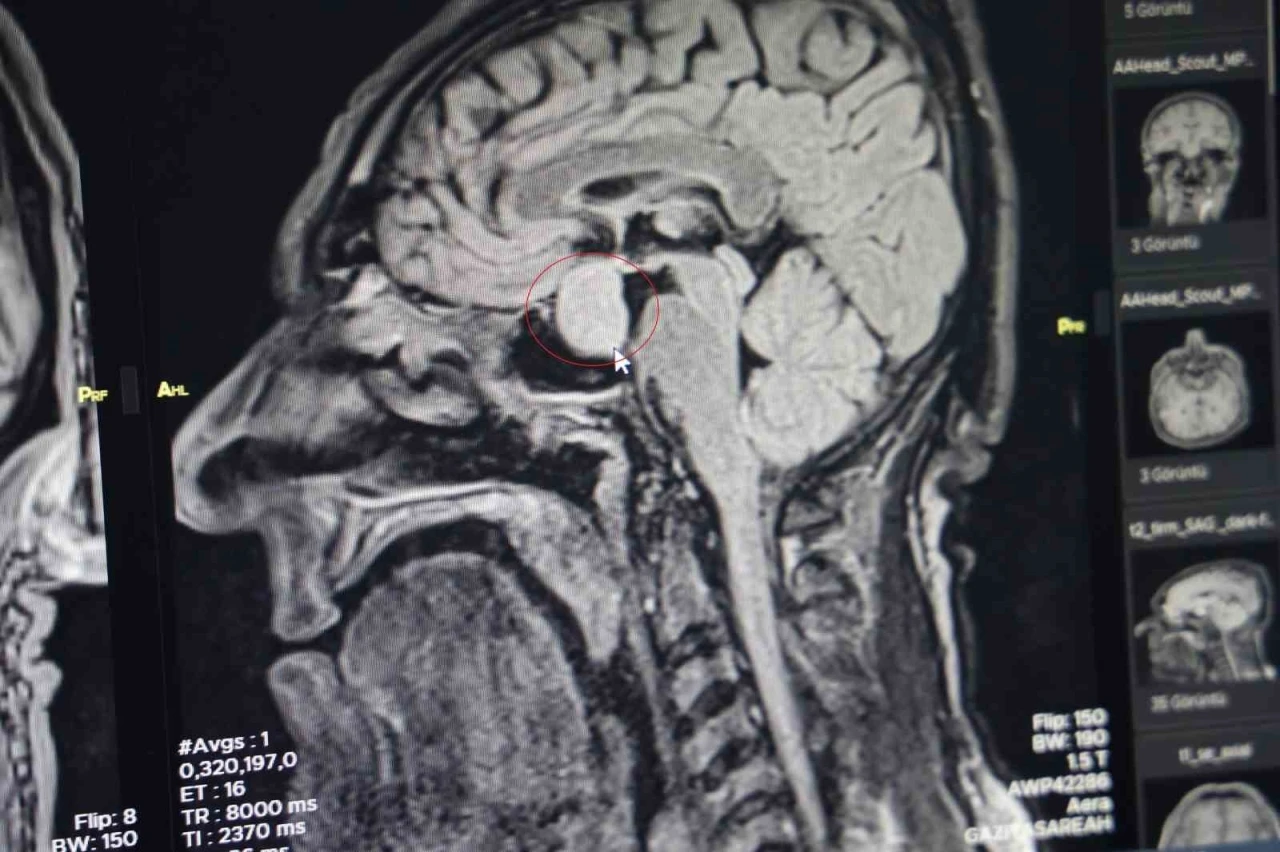

Diyarbakır Gazi Yaşargil Eğitim ve Araştırma Hastanesi Beyin Cerrahi Bölümünde ilk kez beyindeki tümör, kapalı yöntemle alındı.

Hastanın dış merkezlerde çekilen MR’larında hipofiz bölgesinde bir iyi huylu tümör tespit edilmesi ve tavsiye üzerine kliniğine başvurduğunu belirten Dr. Çetin, hastanın yatışını yapıp ileri tetkiklerini yaptıklarını kaydetti.

Dr. Çetin, hormonlarına baktıklarında hastanın büyüme hormonları yüksek olduğunu söyleyerek, "Hastayı yapacağımız ameliyat ile ilgili bilgilendirdik. Hastanemizde ilk defa burundan kapalı yöntemle girilerek hipofiz tümörüne müdahale ettik. Allah’a şükür sağ salim bir şekilde, her hangi bir komplikasyon gelişmeden tümörü aldık. İki gün sonra da hastamızı taburcu ettik. Operasyonumuz 2-2,5 saat sürdü. Herhangi bir riskle karşılaşmadık. Hastamızın genel durumu şu an gayet iyi. Kan tetkiklerinde ve hormon düzeyinin de düştüğünü büyük bir memnuniyetle gözlemledik" dedi.

"Kendi açımız ve hastanemiz açısından güzel oldu, gururlandık" diyen Dr. Çetin, "Hipofiz bezinde yetmezlik ve görme sinirlerinde baskı yaptığı zaman görme kaybına neden olabilmektedir. Bu hastamızda ameliyat öncesi görme kaybı bir miktar vardı. Büyüme hormonu oldukça yüksekti. Tümörü boşalttığımız için hormon düzeyi yarıya düştü. 2-3 hafta sonra kontrole gelecek bir daha ölçme imkanı bulacağız. Bu hastalar genelde şimdiye kadar büyükşehirlere gitmekteydiler. Bundan sonra bu tür ameliyatları gerçekleştirme imkanı bulacağız" şeklinde konuştu.